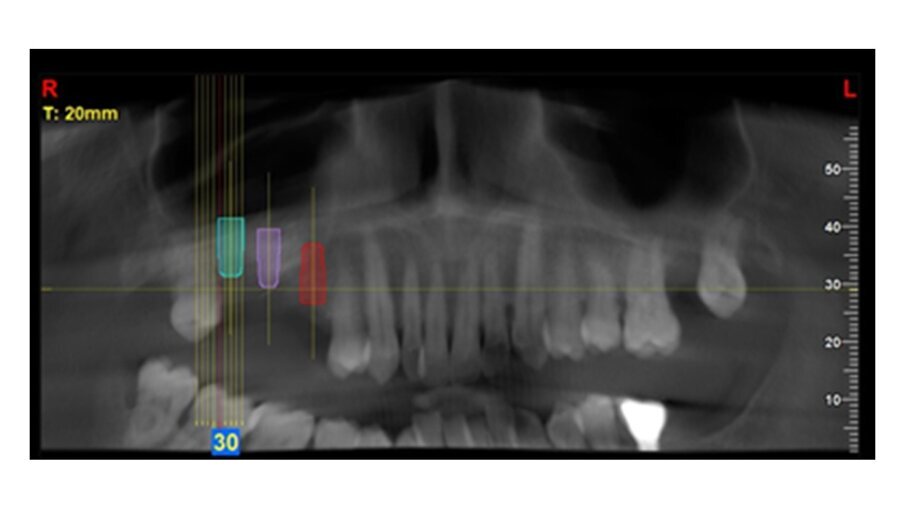

Una paziente donna di 63 anni, con osteoporosi ed ipotiroidismo, si presenta con assenza del 16 e 17, richiedendo riabilitazione dentale fissa. Si procede con l’esecuzione della CBCT per avere dettagli maggiori. Dall’analisi della CBCT nell’area edentula si misura un’altezza ossea verticale <5 mm in zona 16-17 e si nota la presenza di una lesione periapicale dell’elemento dentale 15 (Figg. 1-3). Quindi si programma l’intervento per l’estrazione del 15 e l’intervento per l’esecuzione del rialzo del seno mascellare con approccio laterale, con uso di osso bovino collagenato e spugnette di fibrina, al fine di ottenere l’incremento di osso verticale6. Dopo 5 mesi dall’esecuzione del rialzo di seno mascellare si esegue CBCT di controllo, per verificare l’effettivo aumento di osso verticale e programmare l’inserimento implantare (Figg. 4, 5).